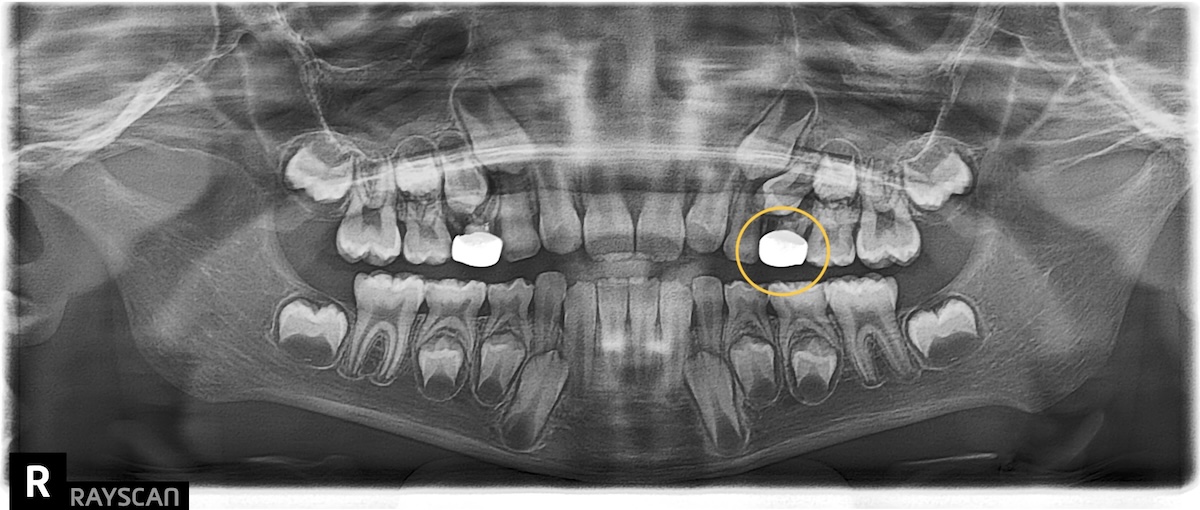

最讓家長擔心的是,努拉不只是乳牙受損,連剛長出來的恆牙大臼齒也出現了蛀牙跡象。陳醫師提到:「這年紀的孩子若伴隨長期鼻塞,習慣用口呼吸,口腔環境會偏酸,這也是導致努拉全口出現 8 顆蛀牙的原因之一。」對於一位常需要面對鏡頭的小演員來說,這不僅是健康問題,更是自信笑容的保衛戰。

What worried her parents most was that not only were her baby teeth damaged, but even her newly erupted permanent molars showed signs of decay. Dr. Chen mentioned: "Children of this age who suffer from chronic nasal congestion often develop a habit of mouth breathing, which creates an acidic oral environment. This is one reason why Nuala had eight cavities throughout her mouth." For a young actress who frequently faces the camera, this isn't just a health issue—it's a battle to protect her confident smile.

把握黃金階段:引導恆牙的「精準導航」

「早期矯正的真諦,是在骨骼最有彈性時,為未來鋪路。」陳醫師強調。努拉左上小臼齒在骨頭內的位置不理想,透過隱適美精確的推力,我們能提早為這些尚未冒頭的恆牙「開路」。現在透過數位科技引導樹苗生長的方向,遠比長大後骨骼定型才硬行移動要來得輕鬆。這不僅降低了未來二次矯正的複雜度,更是送給努拉一份陪伴一輩子的自信底氣。

Seizing the Golden Stage: Precision Navigation for Permanent Teeth. "The true essence of early orthodontics is to pave the way for the future while the bones are at their most flexible," Dr. Chen emphasized. The position of Nuala's upper left premolar inside the bone was not ideal. With the precise thrust of Invisalign, we can "clear the path" early for these teeth that haven't emerged yet. Using digital technology to guide the direction of growth now is much easier than trying to force movement after the bones have set in adulthood. This not only reduces the complexity of future treatments but also gives Nuala a foundation of confidence that will last a lifetime.